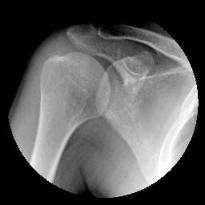

• 核磁共振 & X-Ray 所照出來的圖片

關節唇撕裂傷

X-Ray

• (28,091)【事件簿】我的『關節唇撕裂傷』

• [22/07/13] 訪客 於文章「【事件簿】我的『關節唇撕裂傷』...」留言:

我也是2014年牛棚丟第一球就感覺整個肩膀扯了出去,疼痛不已...

請問版主有朋友動過肩關節鏡手術的嗎? 本人三個月前手術到現在...

您好! 想請問一下盂唇修補手術的部分大概花費多少呢QQ?...